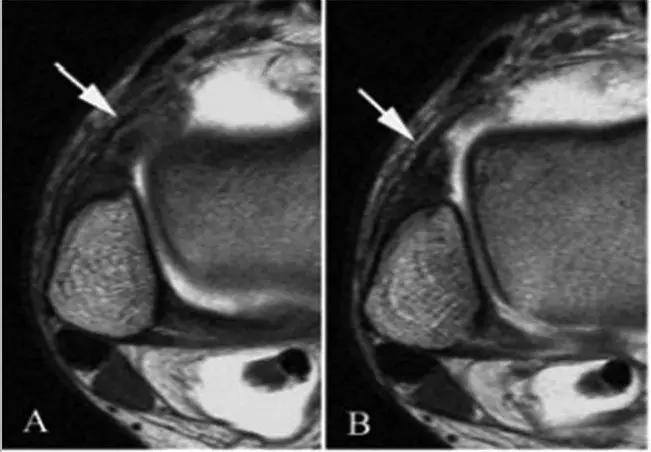

3、MR表现:

- 三角籽骨或距骨后三角结构模糊和变形,T1WI信号降低, T2WI信号升高,

- 周围脂肪水肿,

- 踇趾长屈肌腱信号升高,见鞘膜积液,

- 胫骨后下跟骨上缘骨结构形态变化和信号异常,

- 三角籽骨和距骨退行性囊变。